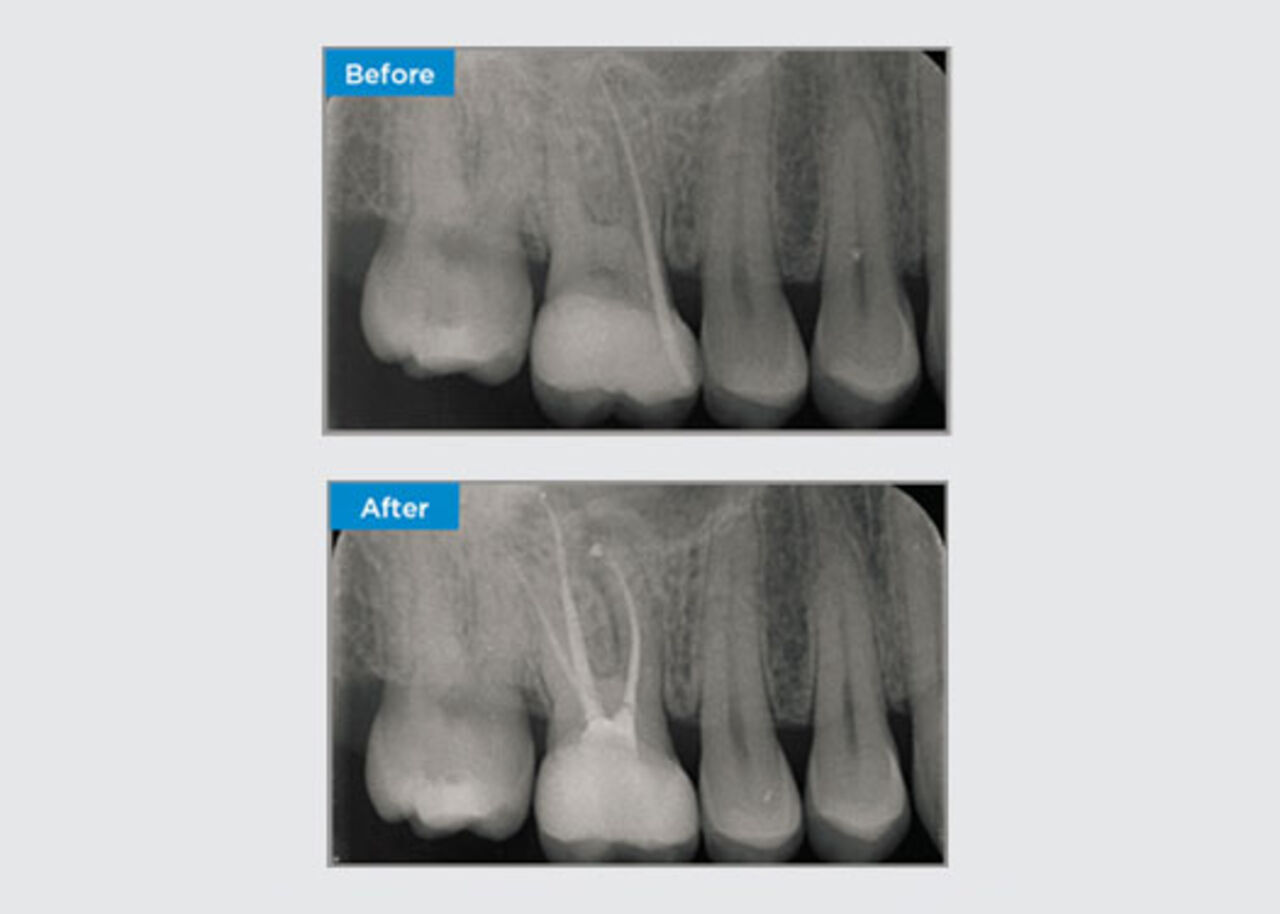

Clinical Cases

Clinicians far and wide, throughout Australia and New Zealand kindly share relevant, interesting and sometimes challenging patient presentations, along with their selection of materials and methods to optimise their patients' outcomes.